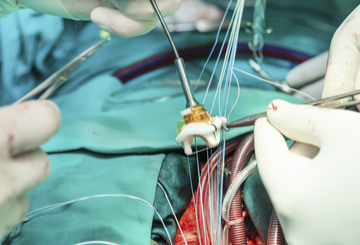

非常高兴地宣布并邀请您参加第十二届国际 DIP 暨展览会FemTech 创新围产期医学研讨会:改善全球孕产妇后代健康于 2024 年 5 月 23-25 日举行意大利索伦托,自第一次第一次 会议以来,DIP 研讨会取得了巨大发展,涵盖了 80 多年的知识、创新研究和最新进展-最新的工具、技术和综合方法。DIP 是母婴医学领域的领先研讨会,提供数据和管理方案,以确保合并糖尿病、高血压和代谢综合征的妊娠获得最佳结果。

与之前的会议一样,第 12 届 FemDIP 研讨会将重点介绍怀孕的进展:从怀孕前、三个月到临产、分娩和产后护理,还将创建一座连接医疗/科学和女性科技社区的桥梁。研讨会的初创企业馆 将为初创企业提供与行业关键人物交流的机会。重点关注妊娠并发症(高血糖、高血压、先兆子痫、早产、非传染性疾病)和妊娠、胎儿生长等的预测和预防,以及未来非传染性疾病的周期这始于子宫内的生活——影响到母亲和后代。我们将扩展到不断发展的女性科技领域,这将丰富科学项目,增加初创企业和投资者之间的交流机会,当然,还会鼓励分享知识以改善生活质量,为那些最需要帮助的人。

研讨会由来自世界各地的知名专业人士和从业人员、孕产妇、胎儿和新生儿医学、基础科学、营养学、助产学、糖尿病、护士教育工作者等领域的领导者组成,研讨会将展示最新的临床和实验室知识革命,基于证据和实践经验。